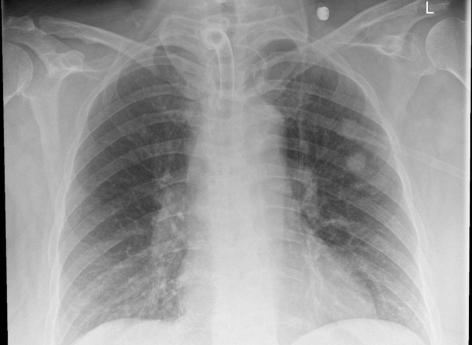

Pour localiser le morceau d’écouvillon, un scanner a été pratiqué qui, au départ, n’a rien montré d’anormal. Un nouveau scanner a ensuite mis en évidence des signes d’inflammation dans un poumon, ainsi qu’un rétrécissement des voies respiratoires.